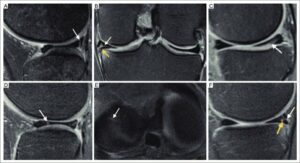

Diagnostic Tests – Meniscus Tears

A physical examination may be followed up by analysis of effusion using arthrocentesis. Fluid is analyzed for blood, bacteria, glucose, protein and cells. Arthrocentesis can also be used to drain excess effusion. Imaging (e.g., x-ray, arthrography, MRI) are used to assess the tear and any other damage as well as rule out fractures and arthritis. Imaging plays an important role in determining treatment options. Arthroscopy can be used during assessment and treatment.

- Menisci © V. Vetri, K. Dragnevski, M. Tkaczyk, M. Zingales, G. Marchiori, N. F. Lopomo, S. Zaffagnini, A. Bondi, J. A. Kennedy, D. W. Murray & O. Barrera is licensed under a CC BY-SA (Attribution ShareAlike) license

- Knee-MR-imaging-of-types-of-meniscal-tears-A-longitudinal-tear-The-sagittal-FS_W640 © Francisco EspinosaKarla V. Rodriguez-AlanisKarla V. Rodriguez-Alanis is licensed under a CC BY-NC-ND (Attribution NonCommercial NoDerivatives) license